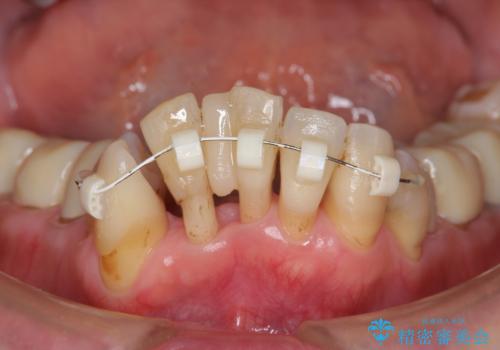

- 上顎前歯の黒ずみの改善、下顎前歯の十度なガタつき、矯正治療とセラミック治療を含む全体的な治療を希望され来院されました。

銀歯を高強度の仮歯に替えたのち、下顎前歯のみの部分矯正→全体的なマウスピース矯正治療(インビザライン)→最終的なセラミック治療と治療を進めます。